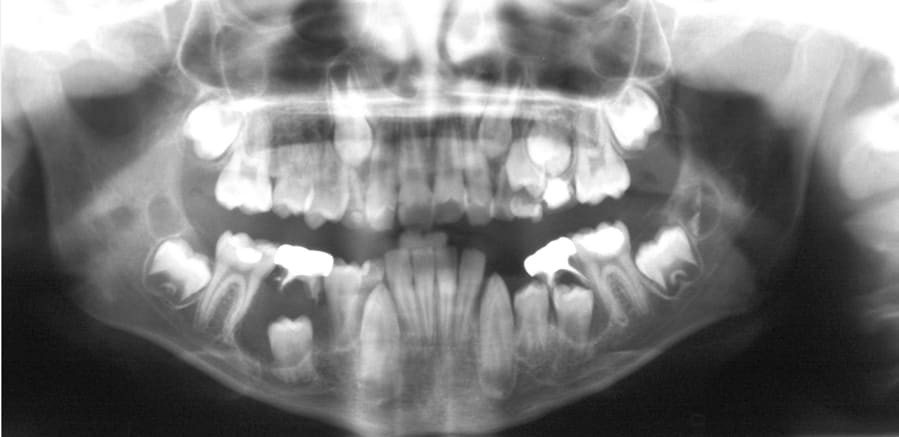

What is a dentigerous cyst?

Dentigerous cysts are the second most common type of odontogenic cyst, which is a fluid-filled sac that develops in the jaw bone and soft tissue. They form over the top of an unerupted tooth, or partially erupted tooth, usually one of your molars or canines. While dentigerous cysts are benign, they can lead to complications, such as infection, if left untreated.

What are the symptoms?

Smaller dentigerous cysts might not cause any symptoms. However, if the cyst grows larger than 2 centimeters in diameter, you may notice:

swelling

tooth sensitivity

tooth displacement

If you look inside your mouth, you may also notice a small bump. If the cyst causes tooth displacement, you might also see gaps slowly forming between your teeth.

What causes it?

Dentigerous cysts are caused by a buildup of fluid over the top of an unerupted tooth. The exact cause of this buildup is unknown.

While anyone can develop a dentigerous cyst, they’re more commonTrusted Source in people who are in their 20s or 30s.

How is it diagnosed?

Small dentigerous cysts often go unnoticed until you have a dental X-ray. If your dentist notices an unusual spot on your dental X-ray, they may use a CT scan or MRI scan to make sure it’s not another type of cyst, such as a periapical cyst or an aneurysmal bone cyst.

In some cases, including when the cyst is larger, your dentist may be able to diagnose a dentigerous cyst just by looking at it.

How is it treated?

Treating a dentigerous cyst depends on its size. If it’s small, your dentist might be able to surgically remove it along with the affected tooth. In other cases, they might use a technique called marsupialization.

Marsupialization involves cutting open the cyst so it can drain. Once the fluid has drained, stitches are added to the edges of the incision to keep it open, which prevents another cyst from growing there.

What are the complications?

Even if your dentigerous cyst is small and not causing any symptoms, it’s important to have it removed to avoid complications. An untreated dentigerous cyst can eventually cause:

infection

tooth loss

jaw fracture

ameloblastoma, a type of benign jaw tumor.

Living with a dentigerous cyst

While dentigerous cysts are usually harmless, they can lead to several problems if left untreated. Talk to your dentist about any swelling, pain, or unusual bumps in your mouth, especially around your molars and canines. In most cases, dentigerous cysts are easy to treat, either through excision or marsupialization.